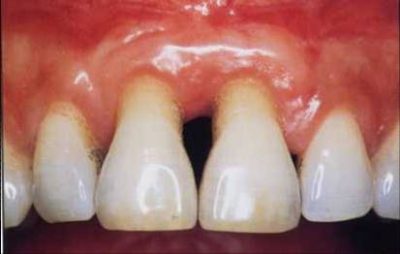

Parodontitis ist eine Entzündung des Zahnfleisches, die durch Bakterien ausgelöst wird. Sie ist die häufigste Form einer Zahnhalteapparaterkrankung. Hierbei vertiefen sich die Zahnfleischtaschen, das knöcherne Zahnfach bildet sich zurück und die Zahnwurzel verliert an Halt. Bei der Parodontitis unterscheidet man zwei Formen der Erkrankung:

Eine Parodontitis entsteht in der Regel durch eine nicht hinreichende Mundreinigung und Pflege der Zähne. Zwischen den Zähnen und dem Zahnfleisch bzw. in den Zahnfleischtaschen bilden sich Bakterien, die als Plague oder Biofilm bezeichnet werden. Die aus dem bakteriellem Stoffwechsel freigesetzten Substanzen führen zu einer Entzündung des Zahnfleisches. Wie jede andere Entzündung im Körper auch, reagiert der Körper auf diese und das Immunsystem wird aktiv. Als Reaktion tritt Zahnfleischbluten auf, da das Immunsystem Enzyme bildet, die die Bakterien zerstören, dabei aber auch gesunde Zellen des Zahnfleisches angreifen und es somit zur Blutung kommt.

Im weiteren Verlauf der Krankheit kommt es zu einem Rückgang des Zahnfleisches, zur Vertiefung der Zahnfleischtaschen und zuletzt zur Lockerung und Ausfall der Zähne. Neben der mangelnden Mundhygiene gibt es noch weitere Ursachen, wie Rauchen, Medikamente oder Diabetis mellitus. Eine Ansteckung von Mensch zu Mensch wird ebenfalls nicht ausgeschlossen.